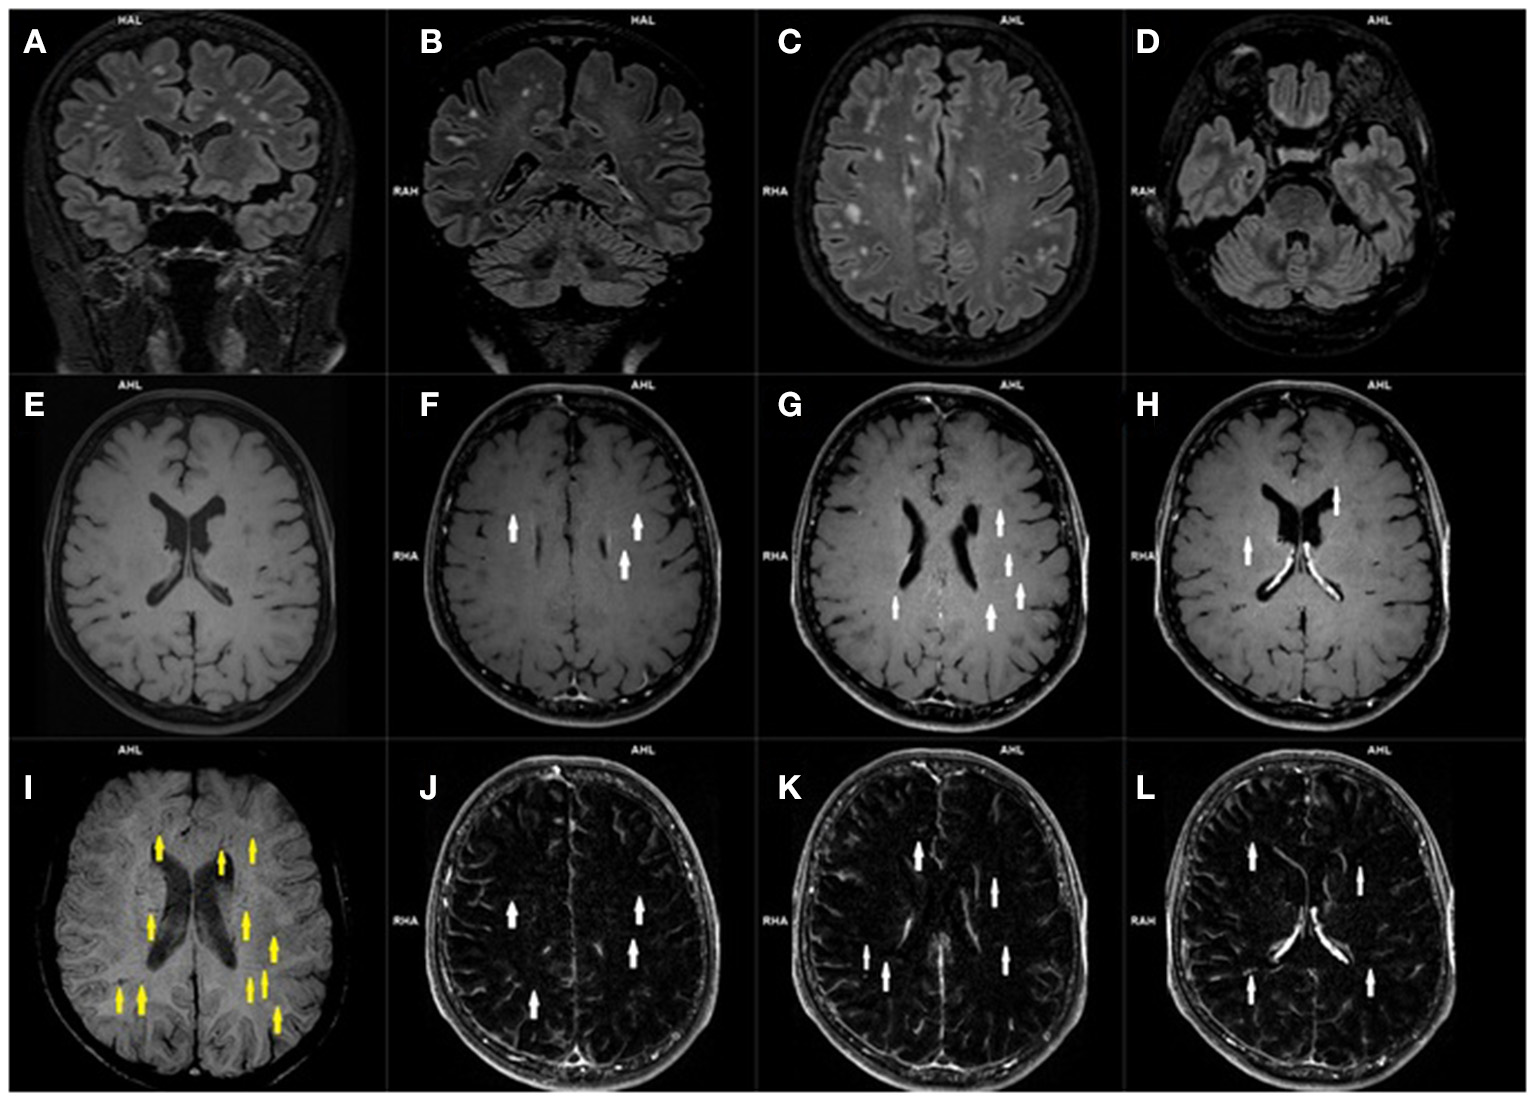

The cerebrovascular alternations in MRI of the CNS in most cases were not related to the neurological symptoms of PCNS (48, 56–58). There were some studies which describes patients with hyperintense subcortical images, as well as in occipital and frontal (bilaterally) white matter in T2-weighted and FLAIR sequences and hypointense lesions on T1-weighted images (48, 56–58). Typical vascular manifestations of PCNS in MR imaging were: an acute brain infarct in striatum, thalamus, pons, occipital lobes, temporal lobes and cerebellum, many small regions of restricted diffusion in the centrum semiovale which indicate a small acute infarction, an acute infarction near the frontal horn, blood vessels occlusion e.g., mild stenosis of the M1 segment, a thrombus in the basilar artery, bilateral P2 segment stenosis, intradural vertebral artery occlusion (48, 52, 53, 56–58). Interestingly, the occurrence of a cerebral vasculitis in the context of PCNS has also been described (48, 57, 58). Figure 4 shows exemplary hyperintensive foci and lesions in the form of engorgement of deep medullary veins and Figure 5 presents vasculitis changes in the form of thickening of the vessel wall, its irregularities and contrast enhancement (Figures 4, 5).

Figure 4

Magnetic resonance imaging of the brain of a patient with post COVID-19 symptoms. Coronal (A, B) and axial (C, D) 3D-FLAIR images demonstrate multiple hyperintensities located within subcortical and deep white matter. Axial precontrast T1-weighted image (E), and contrast enhanced axial T1-weighted images (E–H) with axial T1-weighted subtraction maps (J–L) show subtle parenchymal enhancement along the course of deep located parenchymal veins (white arrows). Corresponding SWI image (I) demonstrates engorged some deep medullary veins (yellow arrows).